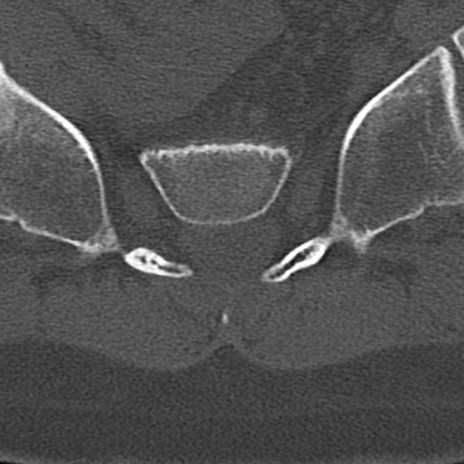

【整形】TIPS症例4 腰椎CT(横断像)

腰椎CT

横断像と矢状断像